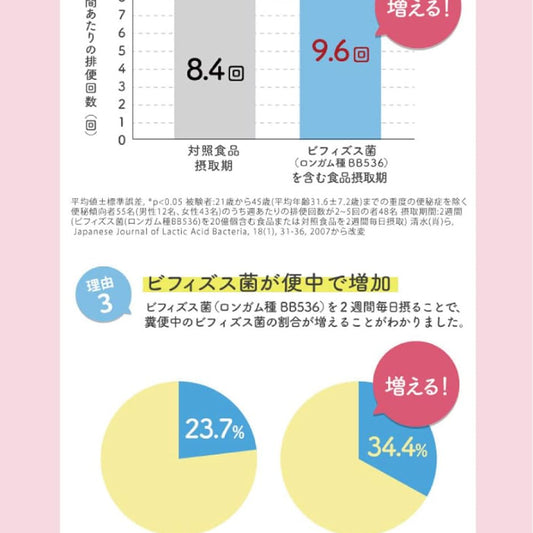

森下仁丹|Health Aid Bifina R 25億 益生菌乳酸菌 (20袋/20日份)【平行進口產品】日本版 R款

森下仁丹|Health Aid Bifina R 25億 益生菌乳酸菌 (20袋/20日份)【平行進口產品】日本版 R款